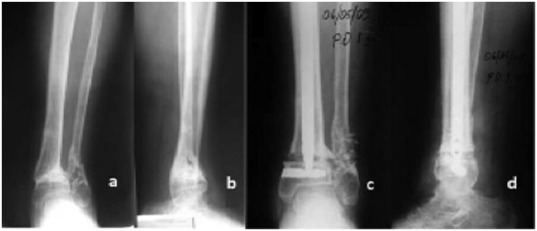

Patient 3

Fig. 4

Fig. 4.

Preoperative AP (a) and lateral (b) , and postoperative AP (c) and lateral (d) X-rays of Patient 3.

The patients were followed up for 3 years (Fig. 5 a and b), 3 months (Fig. 6 a and b), and 6 months (Fig. 7 a and b), respectively. Osteotomies were performed on Patient 1 and Patient 2; nonunion experienced by Patient 3 healed radiologically and clinically within 6 weeks postoperatively. American Orthopaedic Foot and Ankle Society scores were 36, 33, and 21 preoperatively; and 75, 68, and 75 postoperatively in Patients 1, 2 and 3, respectively (Fig. 8 a–d). There was neither propagation of nails into the ankle joint nor implant failure.